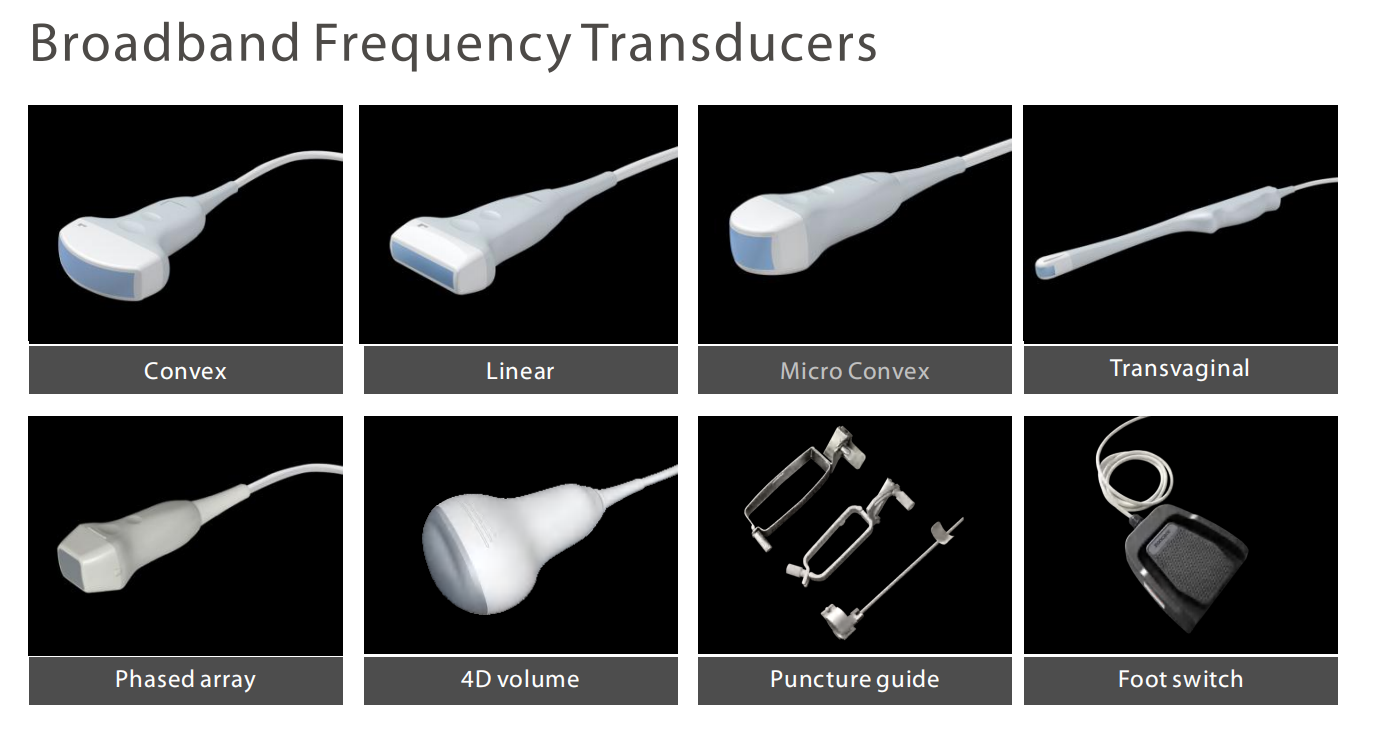

| Sensor port: | 4 sensor ports | thing: | MSLCU46-A |

Active Probe Port | 4 |

Transvaginal Probe Scanning Angle | 150° |